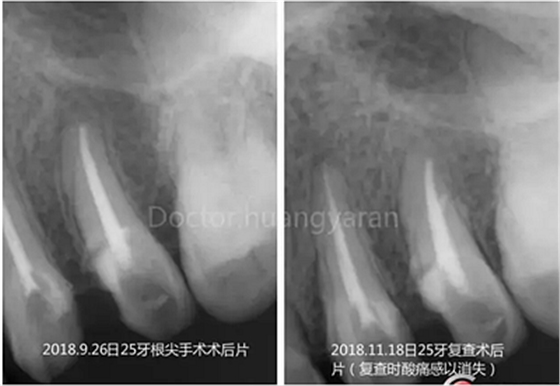

拍攝根尖片檢查,24、25牙根充到位,但考慮到可能是治療過程中消毒不到位導致,所以重新對25牙做根管治療,但酸痛感無減輕,于是考慮到根尖骨穿孔的可能性,與患者溝通后做診斷性翻瓣,翻瓣后發(fā)現(xiàn)根尖處無頰側(cè)骨板直接暴露,當即行根尖切除術(shù),對位縫合,經(jīng)兩個月恢復根尖已無酸痛感!